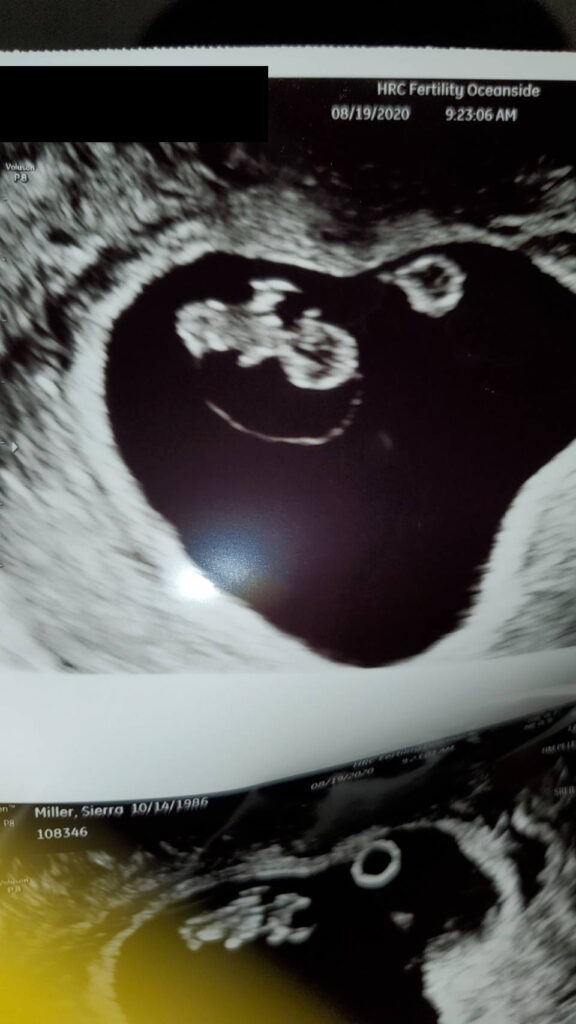

Baby超音波紀錄 : 5週又5天 Posted on August 25, 2020 by yourtesttubebaby 五個禮拜又五天大的小baby就是長的這樣的! ☀ 網站上每位小寶貝都是我們的成功案例,照片皆經父母親許可使用 ( 若未經允許請勿轉載 ) ☀ Posted in Uncategorized